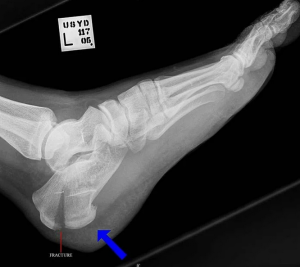

Рекомендовано проводить рентгенографию стопы в одной проекции/двух проекциях в боковой проекции и при необходимости в дополнительных проекциях всем пациентам, которым поставлен диагноз перелома пяточной кости, с целью определения положения костных отломков и определения дальнейшей тактики лечения [49].

Уровень убедительности рекомендаций С (уровень достоверности доказательств - 4) Комментарий. Боковая проекция является обязательной. При недостаточности информации о характере перелома необходимо выполнять дополнительные проекции и КТ исследование пяточных костей (компьютерную томографию кости), [3, 13, 40].